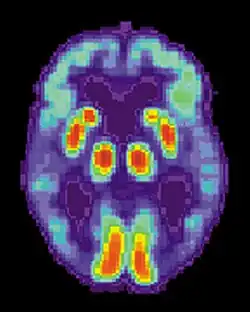

La maladie d'Alzheimer est caractérisée par une perte de neurones et de synapses dans le cortex cérébral et certaines régions subcorticales. Cette perte anormale entraîne une atrophie des régions affectées, incluant le lobe temporal, pariétal et une partie du Lobe frontal et du gyrus cingulaire[62]. Le cerveau peut ainsi perdre 8 à 10 % de son poids tous les dix ans, contre 2 % chez un sujet sain. L'atrophie corticale s'accompagne d'une dilatation des ventricules cérébraux et des sillons corticaux ainsi que d'une perte neuronale affectant particulièrement le système cholinergique (noyau basal de Meynert, septum, cortex entorhinal, amygdale et hippocampe).

Les études utilisant l'IRM et le PET scan ont documenté une réduction de certaines régions spécifiques chez les personnes atteintes de la maladie d'Alzheimer lorsqu'elles progressent d'un trouble cognitif léger vers une maladie d'Alzheimer, en comparaison des images de sujets sains âgés[63],[64].

- L'Imagerie par résonance magnétique (IRM) :

L'IRM permet de détecter une atrophie corticale, notamment une atrophie des hippocampes. Elle permet par ailleurs d'éliminer d'autres causes de démences telles que la présence de lésions vasculaires, d'une tumeur cérébrale ou d'un hématome.

- La Tomographie par émission de positons (TEP)

Elle permet de mettre en évidence un hypo-métabolisme (c'est-à-dire un fonctionnement moins efficace du cerveau) et de visualiser les lésions cérébrales caractéristiques de la maladie, notamment les plaques amyloïdes.